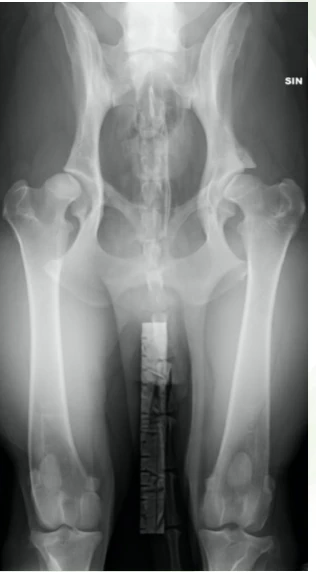

Mikäli epäilet koirallasi lonkkanivelen kasvuhäiriötä, on syytä varata aika eläinlääkärille tutkimukseen. Eläinlääkärissä koiralle tehdään ontumatutkimus, jossa tarkistetaan koiran liikkeet sekä käydään läpi nivelet, luut ja lihakset. Ontumatutkimuksen tarkoitus on löytää kipukohta sekä sulkea pois muita takajalkojen ontumien syitä, kuten ristisidevaurio tai panosteiitti. Ontumatutkimuksen jälkeen koira rauhoitetaan, jotta voidaan kokeilla lonkkanivelen löysyyttä ja ottaa tarvittavat röntgenkuvat.

Röntgenkuva otetaan koiran ollessa selällään. Koiran jalat vedetään suoraksi taakse, jolloin nivelkapseli kiertyy ja tämän seurauksena osittain kiristyy. Nivelkapselin kiristyessä reisiluunpää pysyy paremmin lonkkamaljassa, joten normaalit röntgenkuvat eivät yksinään riitä lievän lonkan kasvuhäiriön tunnistamiseen. Lisätietoa kasvuhäiriöstä antaa niin kutsutut loitonnuskuvat. Loitonnuskuvissa koiran reisiluiden väliin asetetaan laite, jolla reisiluun päitä saadaan työnnettyä pois lonkkamaljasta. Normaali, terve lonkka ei juurikaan liiku paikoiltaan, mutta löysä lonkka liikkuu.

Lonkkanivelen kasvuhäiriö diagnosoidaan useimmiten selällään otettavista röntgenkuvista.